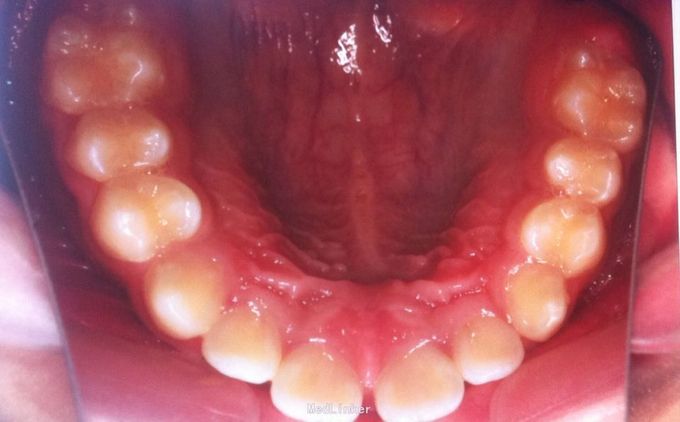

恒牙期 磨牙中性关系 前牙覆合覆盖关系正常 A1B1之间1mm间隙

安氏一类 不拔牙矫治,直丝弓矫治器,排齐整平上下牙列,关闭前牙散在间隙,矫治后磨牙中性关系,前牙正常覆合覆盖,维持现有面型

18、28、38、48存在,必要时拔除